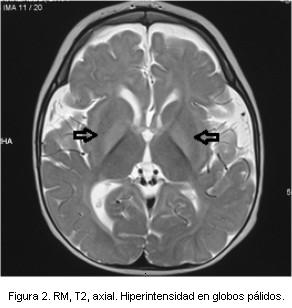

- Resonancia magnética (RM): imágenes hipointensas en T1 e hiperintensas en T2 y FLAIR, mal delimitadas bilaterales y simétricas que comprometen ambos putámenes, globos pálidos, sustancia nigra, núcleos subtalámicos, sustancia gris periacueductal, núcleos dentados y tronco encefálico, con restricción en la difusión. Cuerpo calloso adelgazado y megacisterna magna (figuras 1 y 2).

Las imágenes en la resonancia magnética que se observan de forma más característica en esta enfermedad son lesiones bilaterales y simétricas, hiperintensas en T2 en sustancia blanca periventricular a nivel parietal y occipital, correspondiendo a alteraciones en la mielinización entre otras posibles causas(12-14).

En el paciente las lesiones eran más extensas de lo habitual abarcando ganglios basales, mesencéfalo y pedúnculos cerebelosos medios. En la literatura se describe de forma excepcional dicha topografía lesional; estos hallazgos se vinculan a la elevada concentración del aminoácido en sangre. Así mismo, se describe una mayor extensión lesional en la asociación de PKU con síndrome de West, postulándose que ambas patologías participan alterando el proceso normal de mielinización(11,13).